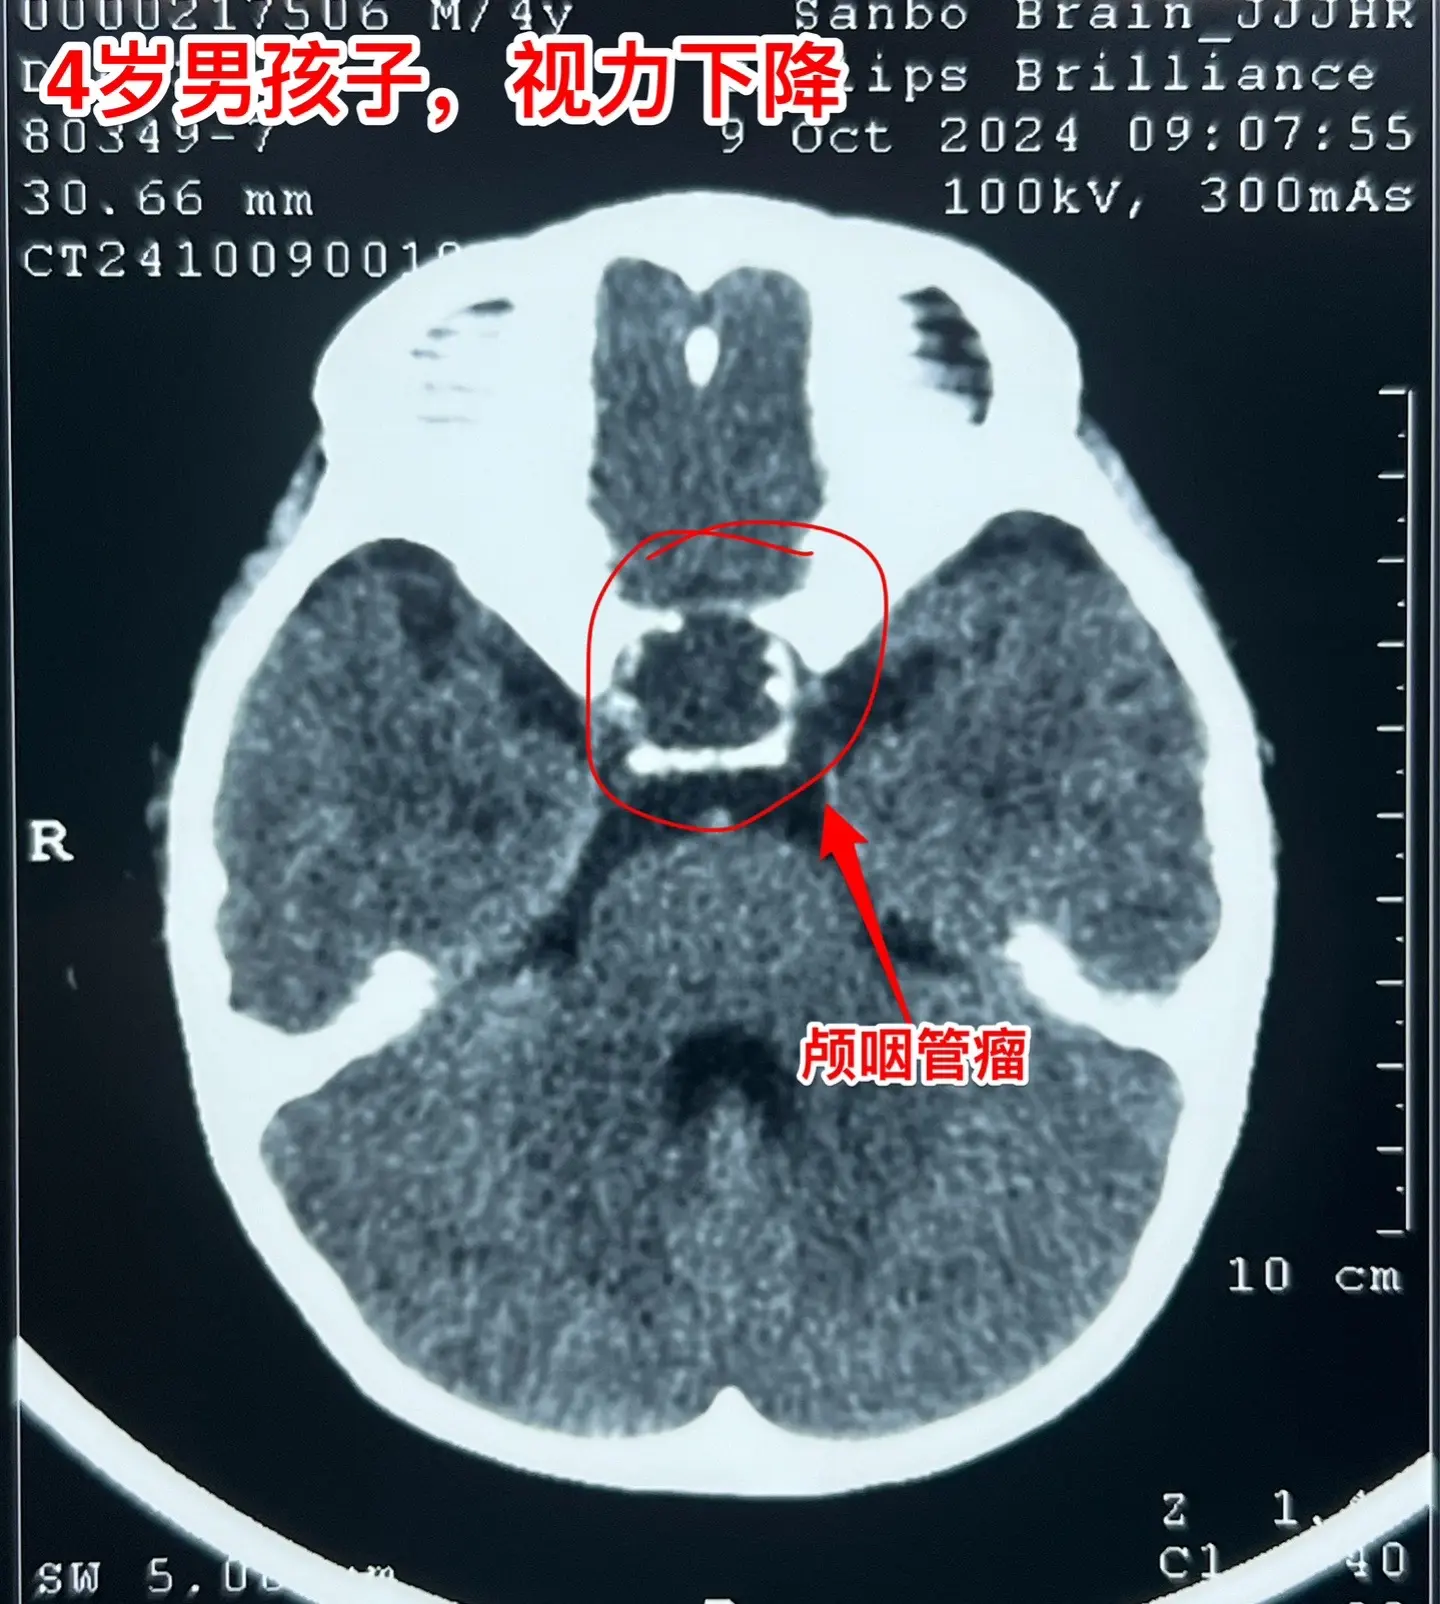

一天完成两个颅咽管瘤手术几乎成了常态。今天的两个颅咽管瘤手术,强度很大哦! 1,4岁男孩子,视力下降。典型的造釉细胞型颅咽管瘤,属于鞍隔下颅咽管瘤。开颅手术将颅咽管瘤完全切除,垂体大部分保留,垂体柄保留,下丘脑保护完好。这样的结果我们很满意! 2,35岁女性,经鼻手术后颅咽管瘤复发,视力下降。是乳头型颅咽管瘤。肿瘤与视交叉粘连很紧,手术分离难度大,最终得到完全切除。